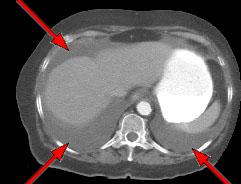

“OMENTAL CAKE” SIGN OF PERITONEAL METASTASIS

HELICAL CT FINDINGS: The CT was performed on AIC’s multi-slice helical CT (MSCT) scanner. Images with 5 mm collimation were obtained before, immediately following and 5-10 minutes after power injection of IV contrast. Fig. 1 demonstrates large bilateral pleural effusions (red arrows) with secondary compressive atelectasis of the lower lobes (yellow arrow). Fig. 2 shows large amount of ascites (arrows). Fig. 3 shows a large heterogeneous complex pelvic mass (blue arrow) and a large amount of peritoneal masses consistent with omental metastasis known as “omental caking” (green arrows).

DIAGNOSIS: The CT images are suggestive of ovarian carcinoma and metastatic peritoneal implants.